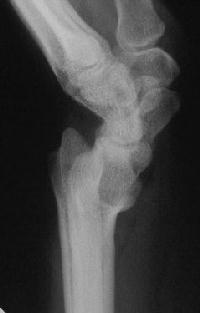

Case 1. Typical Xray findings of congenital Madelungs.